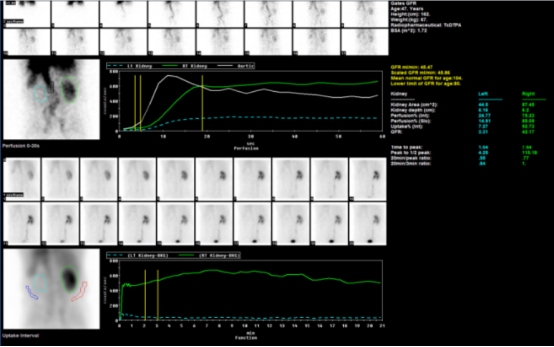

病例1:患者男47岁,2型糖尿病3年,高血压急症入院,经常规治疗血压控制不佳,临床疑诊继发性高血压。尿素:7.7mmol/L,尿酸:467umol/L↑,血肌酐136umol/L↑。血管超声提示:右肾大小正常,血流分布偏少;左肾萎缩?主动脉CTA示:主动脉夹层(Stanford B型),左肾动脉纤细,右肾动脉造影剂充盈良好。行肾动态显像评价分肾功能如下图。

右肾血流灌注时间正常,右肾实质影像未见异常,右肾肾小球滤过功能正常,GFR值42.17ml/min(正常低限);左肾血流灌注时间明显延迟,左肾实质未见显影,左肾无功能,GFR值3.31ml/min↓;总肾小球滤过率下降,总GFR值45.47ml/min↓。经肾动脉造影证实:左肾动脉闭塞,右肾动脉由真假腔供血,血流通畅。